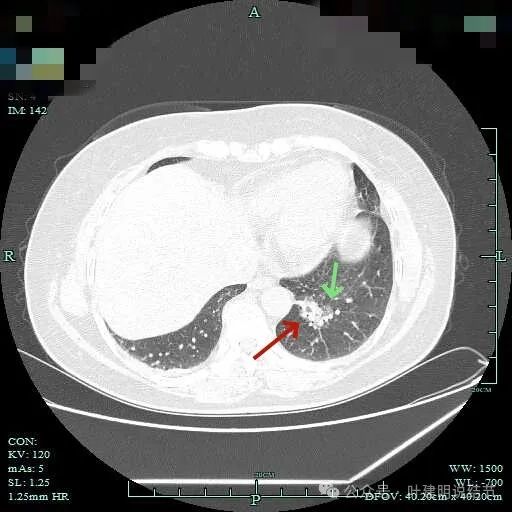

表面浅分叶,磨玻璃成分明显,实性部分密度较高。

表面不平,磨玻璃部分的轮廓与边界清,实性部分占比不小,缺乏收缩力,像是腺泡型。

实性成分占比较高,边上有明显磨玻璃成分,说明含贴亚型。

灶内有小空泡征,磨玻璃部分轮廓与边界清,实性部分虽明显但毛刺征或收缩力等均不明显。